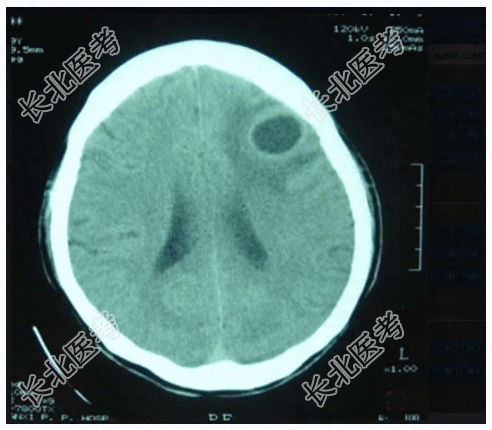

- 多项选择题2.提示:患者颅脑CT平扫如图所示。该患者颅脑CT平扫异常表现包括哪些

A、左额叶类圆形病变

B、左额顶叶类圆形病变

C、左顶叶类圆形病变

D、病变边界较清晰

E、病变无明显边界

F、病变中心为液性成分

G、病变中心为实性成分

H、病变中心为液性和实性混杂成分

I、病变周围明显水肿

J、病变周围无明显水肿